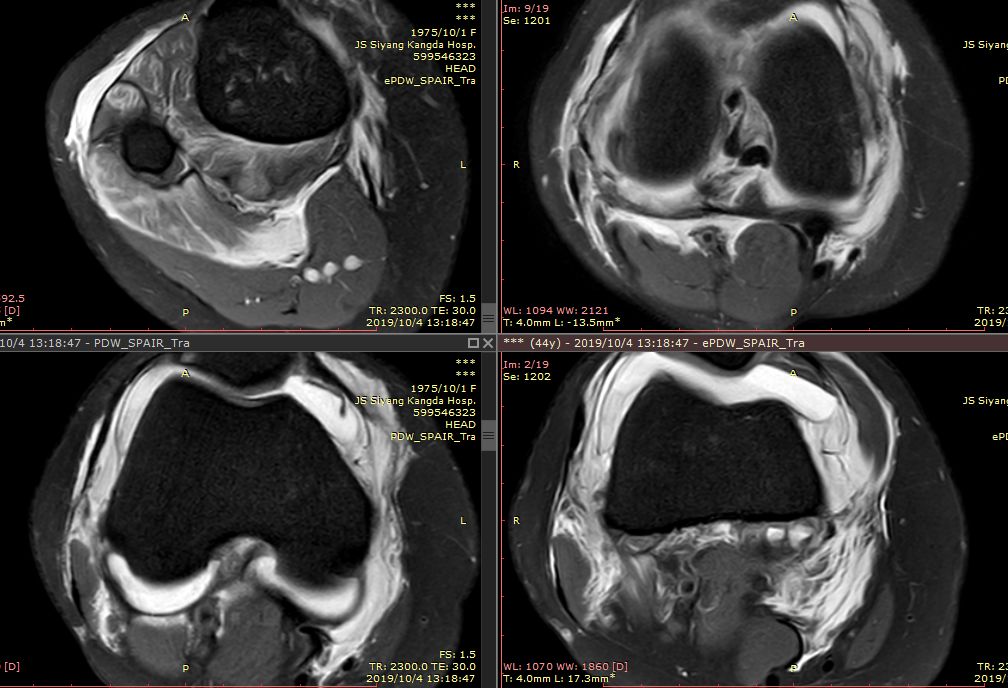

下图横断面的标线标记的是左下图,为外侧半月板的桶柄样撕裂移位

下图标记的是外侧半月板的撕裂

下图示外侧副韧带损伤 腘肌腱损伤 髂胫束连续

内侧副韧带损伤

膝后肌群损伤